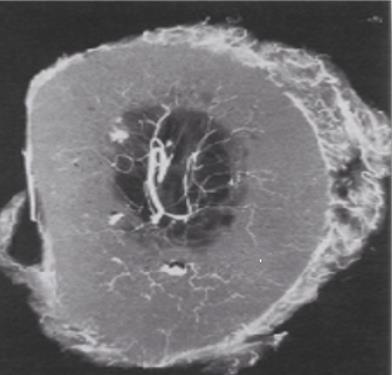

It is well known that vascular supply changes over time Kadiyala, et al. [102]. In toddlers, the vascular supply to the cortex emanates exclusively from the bone marrow (Figure 2). The richly vascularized periosteum is perfectly integrated with the cortex and does not penetrate. At a later age, the quality of vascular supply to bone tends to decline. In this angiographic section of a crosssection of a 42-year-old femur see Figure 3, the robust medullary arteries supply the entire cortex apart from the right part of the posterior cortex where traces of periosteal arteries are detected. Furthermore, the vascularization of the shaft of a mammalian long bone is longitudinal crossing the major axis of the bone in the middle of the bone marrow. Here in Figure 4 there are 2 nutrient systems, one proximal, the other distal.

Figure 2: Angiograph of a transverse section of a femur (2-years-old) perfused in vivo. (Enlargement x3) Brookes, et al. [121].

Figure 3: Angiograph of a transverse section of a femur (42-years-old). (Enlargement x3) Brookes, et al. [121].